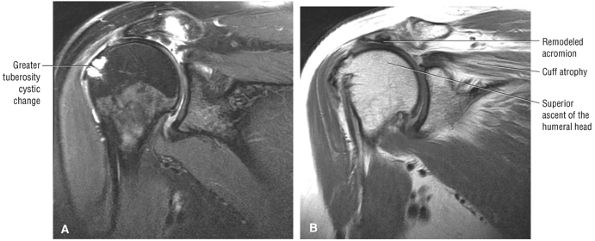

FIGURE 8.102 ● (A) The anterior undersurface of the acromion and the coracoacromial ligament form the coracoacromial arch. The subacromial subdeltoid bursa facilitates the passage of the rotator cuff and proximal humerus under the coracoacromial arch. (B) A superior axial image shows the anterior-to-posterior extent of the coracoacromial (CA) ligament perpendicular to the supraspinatus tendon. The fluid in the subacromial-subdeltoid bursa represents fluid between two serosal surfaces in contact with each other. One serosal surface is contributed by the undersurface of the coracoacromial arch and deltoid, and the other serosal surface is on the bursal side of the cuff.

|

![]() |

FIGURE 8.103 ● Pseudospur. The normal broad attachment of the coracoacromial ligament to the inferior surface of the acromion is shown on (A) T1-weighted coronal oblique and (B) sagittal oblique images. The low-signal-intensity acromial cortex (black arrows) and adjacent coracoacromial ligament and lateral slip of the deltoid attachment (white arrows) give the false impression of a small subacromial spur in the coronal plane. This pseudospur should not be misinterpreted as impingement; otherwise, unnecessary acromioplasties may be performed on patients with a normal coracoacromial ligament attachment and no associated acromial spurs.